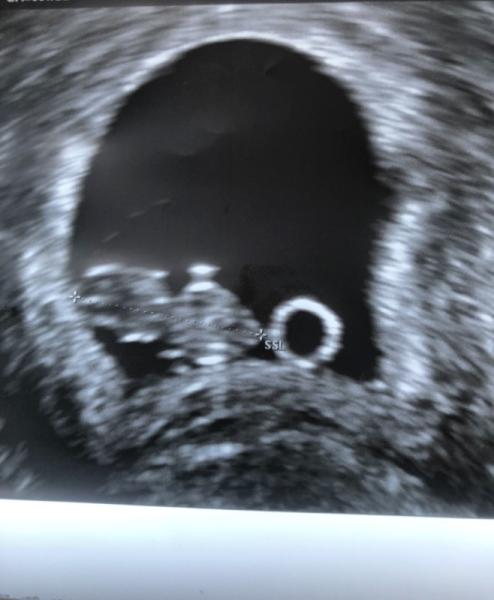

Gestern hatte ich nochmal ein Termin beim FA. da bei 6+0 „nur“ die Fruchthöhle und einen kleinen Punkt zu sehen gab. Und gestern dann die Erleichterung, konnte das Baby super sehen. Ist 1,5cm groß und Herzchen hat schön geschlagen. Es hat auch schon Ansätze für Arme und Beine. Pures Glück das zu sehen. Nächster Termin am 7.10, hasse die Wartezeit dazwischen.

Bild zu Gestern Termin FA - Forum für April - Mamis

Na das ist doch schön. Hat man was zu dem Kreis unterm Embryo gesagt?

Der Kreis ist der Dottersack.

Das ist der Dottersack. Bei meinem US bei 8+4 wars genauso, nur sah der Dottersack ne Spur kleiner aus. Ärztin sagte damals Embryo Dottersack Fruchthöhle hat alles perfekte Größe